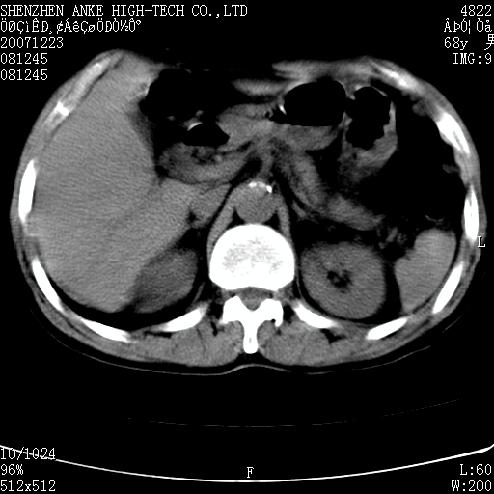

平扫未见明确异常

上腹部ct平扫未见明显异常。

上腹部ct平扫未见明显异常

上腹部ct平扫未见明显异常。(肠道气体较多,患者呼吸了)

平扫未见明确异常.